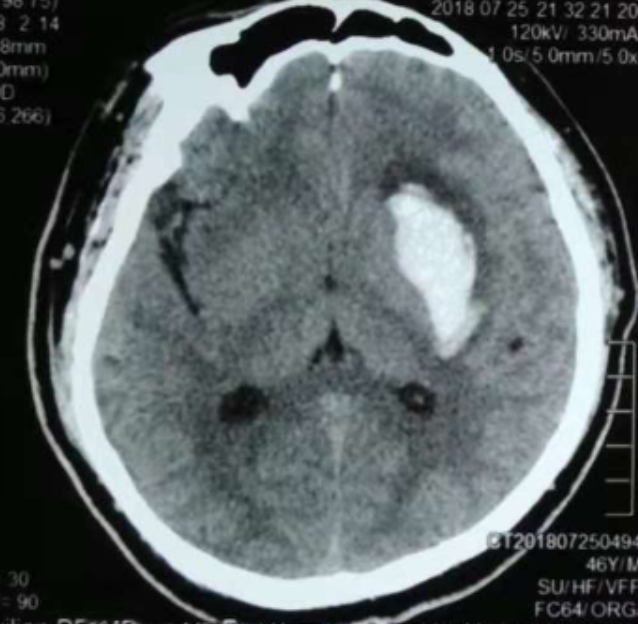

3個(gè)月前CT:腦出血